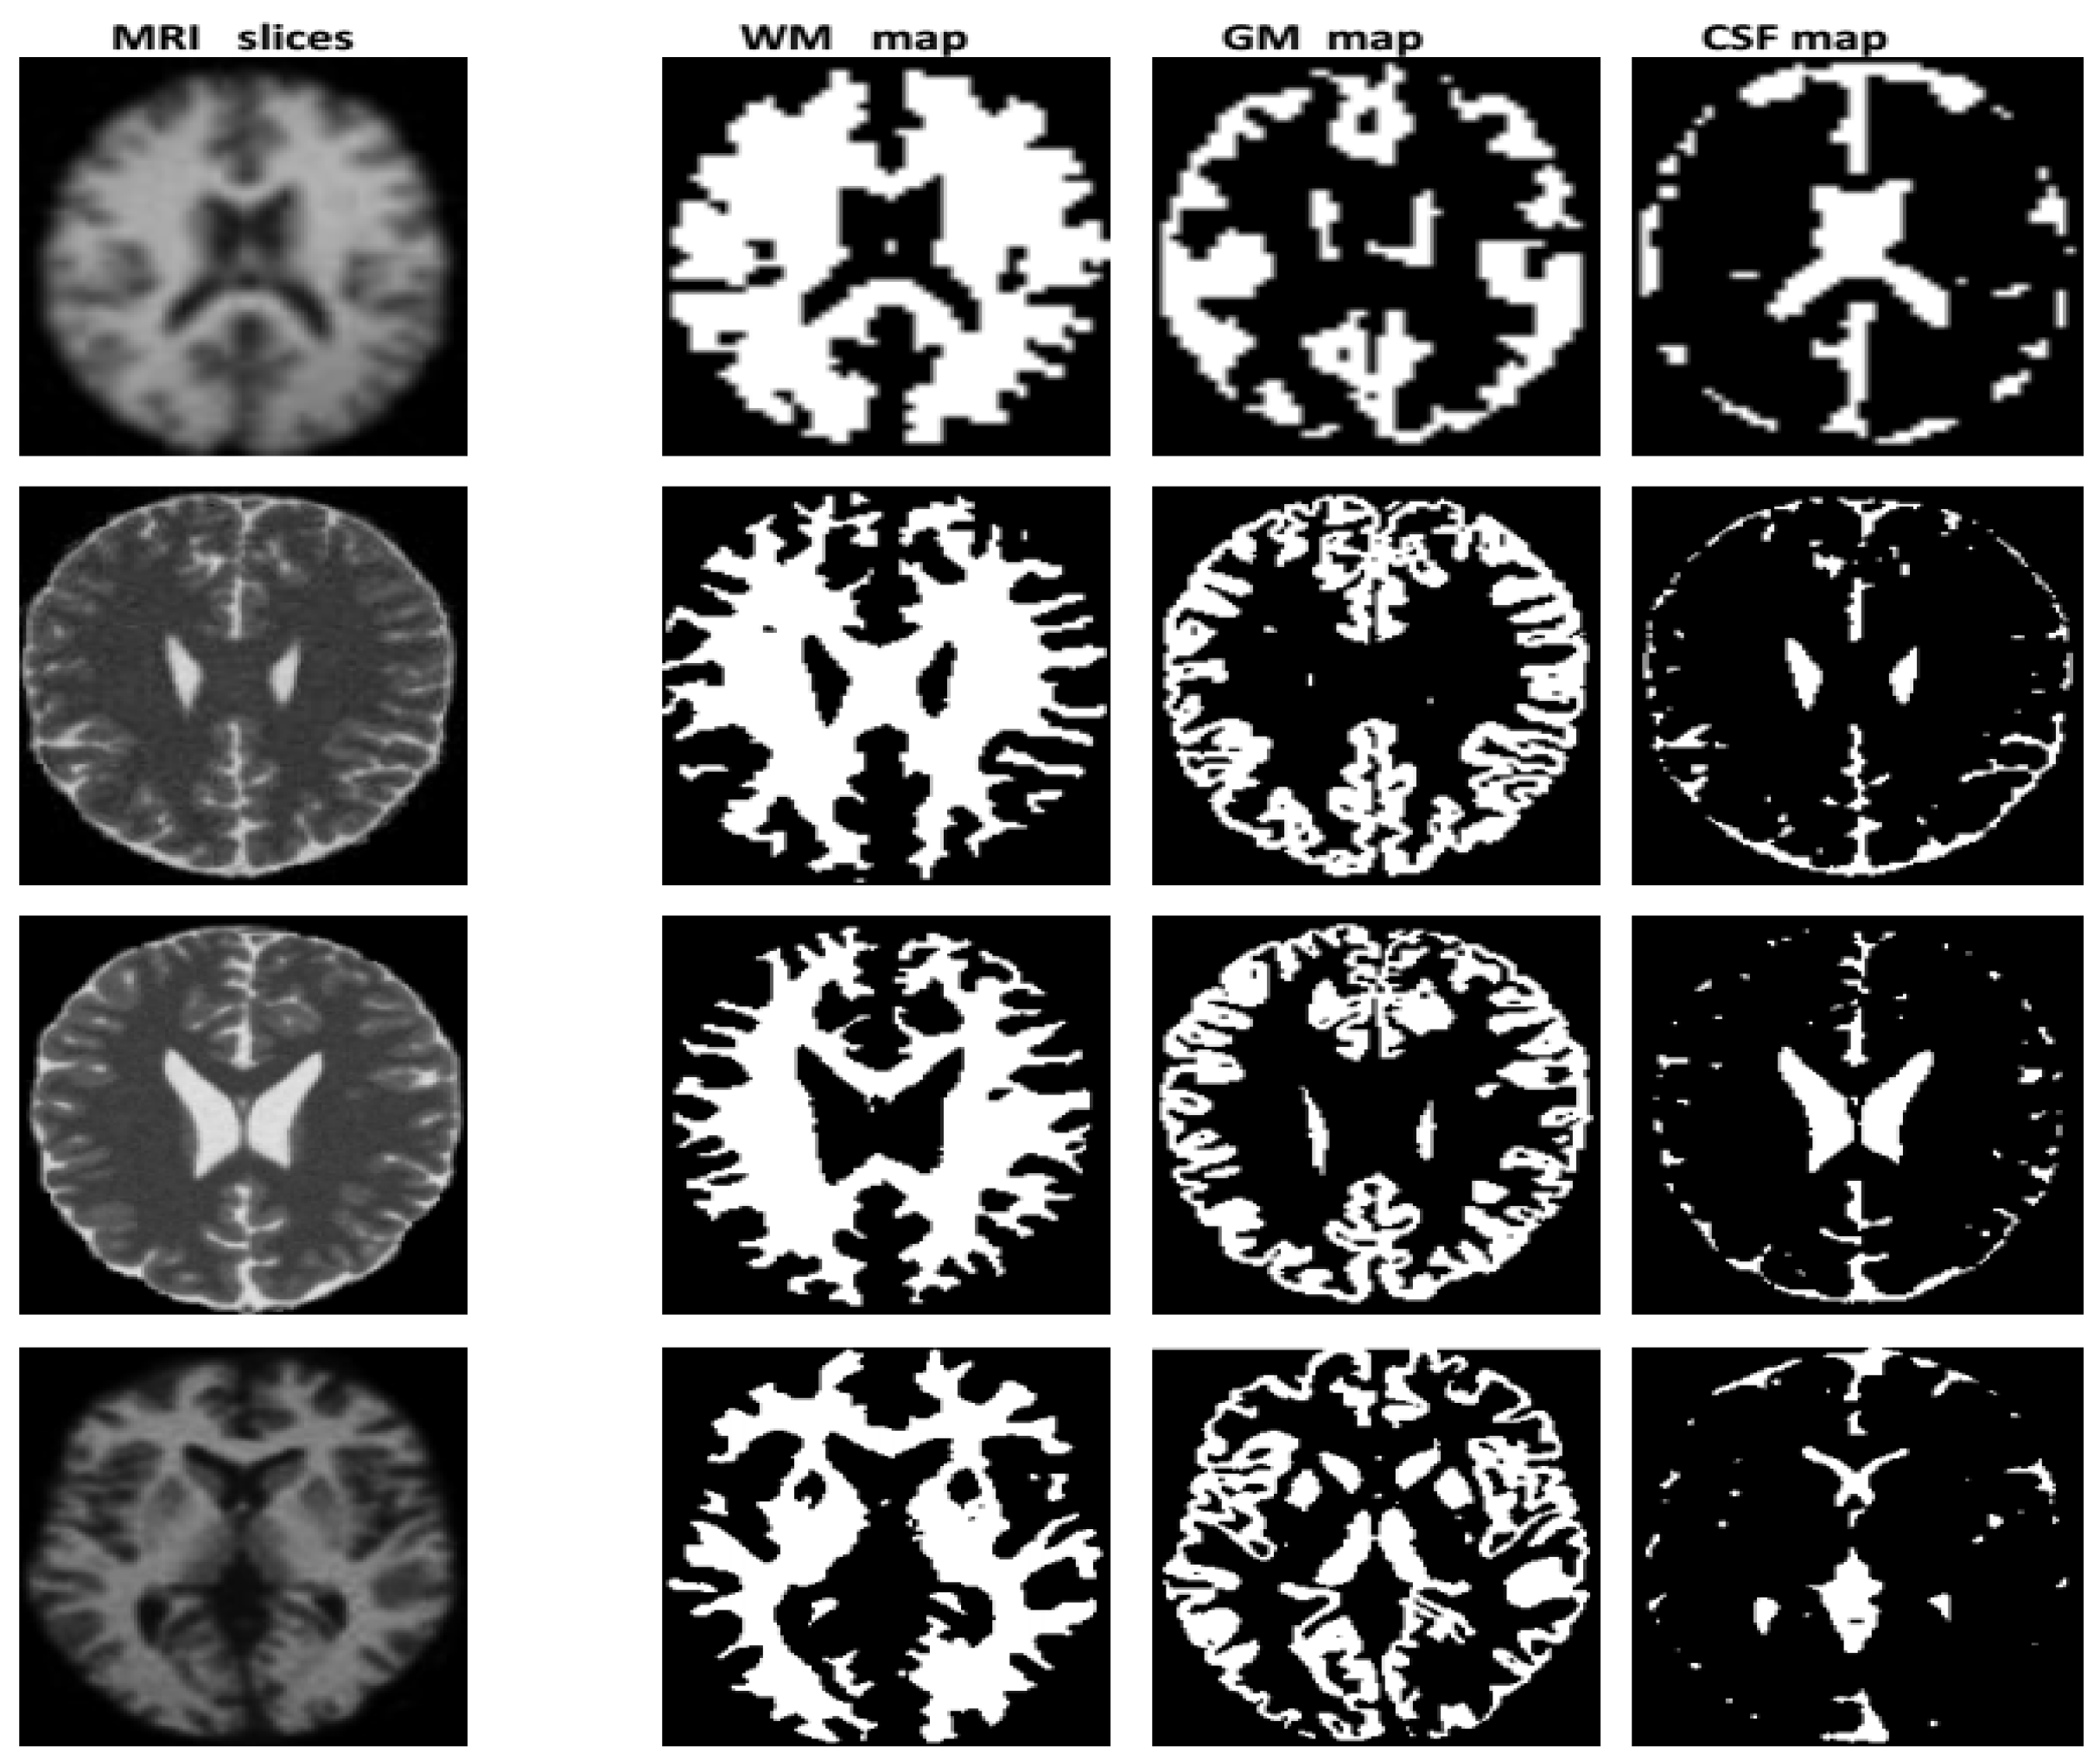

3.2. Segmentation

3.2.2. Fusion

3.2.3. Decision

Image Labeling

Synthetic Image